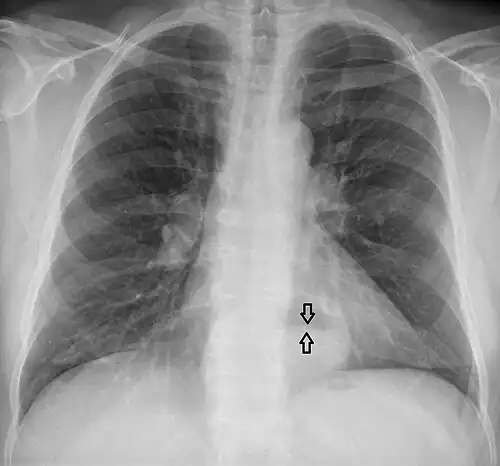

A large hiatal hernia on chest X-ray marked by open arrows in contrast to the heart borders marked by closed arrows

-

This hiatal hernia is mainly identified by an air-fluid level (labeled with arrows). -